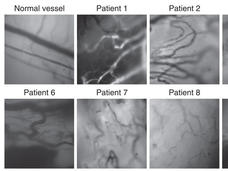

High-Magnification Microscopy Visualizes Tumor Blood Vessels in Real Time

High-powered intravital microscopy reveals that 50 percent of blood vessels in melanoma tumors do not have any blood flow, according to a new study.